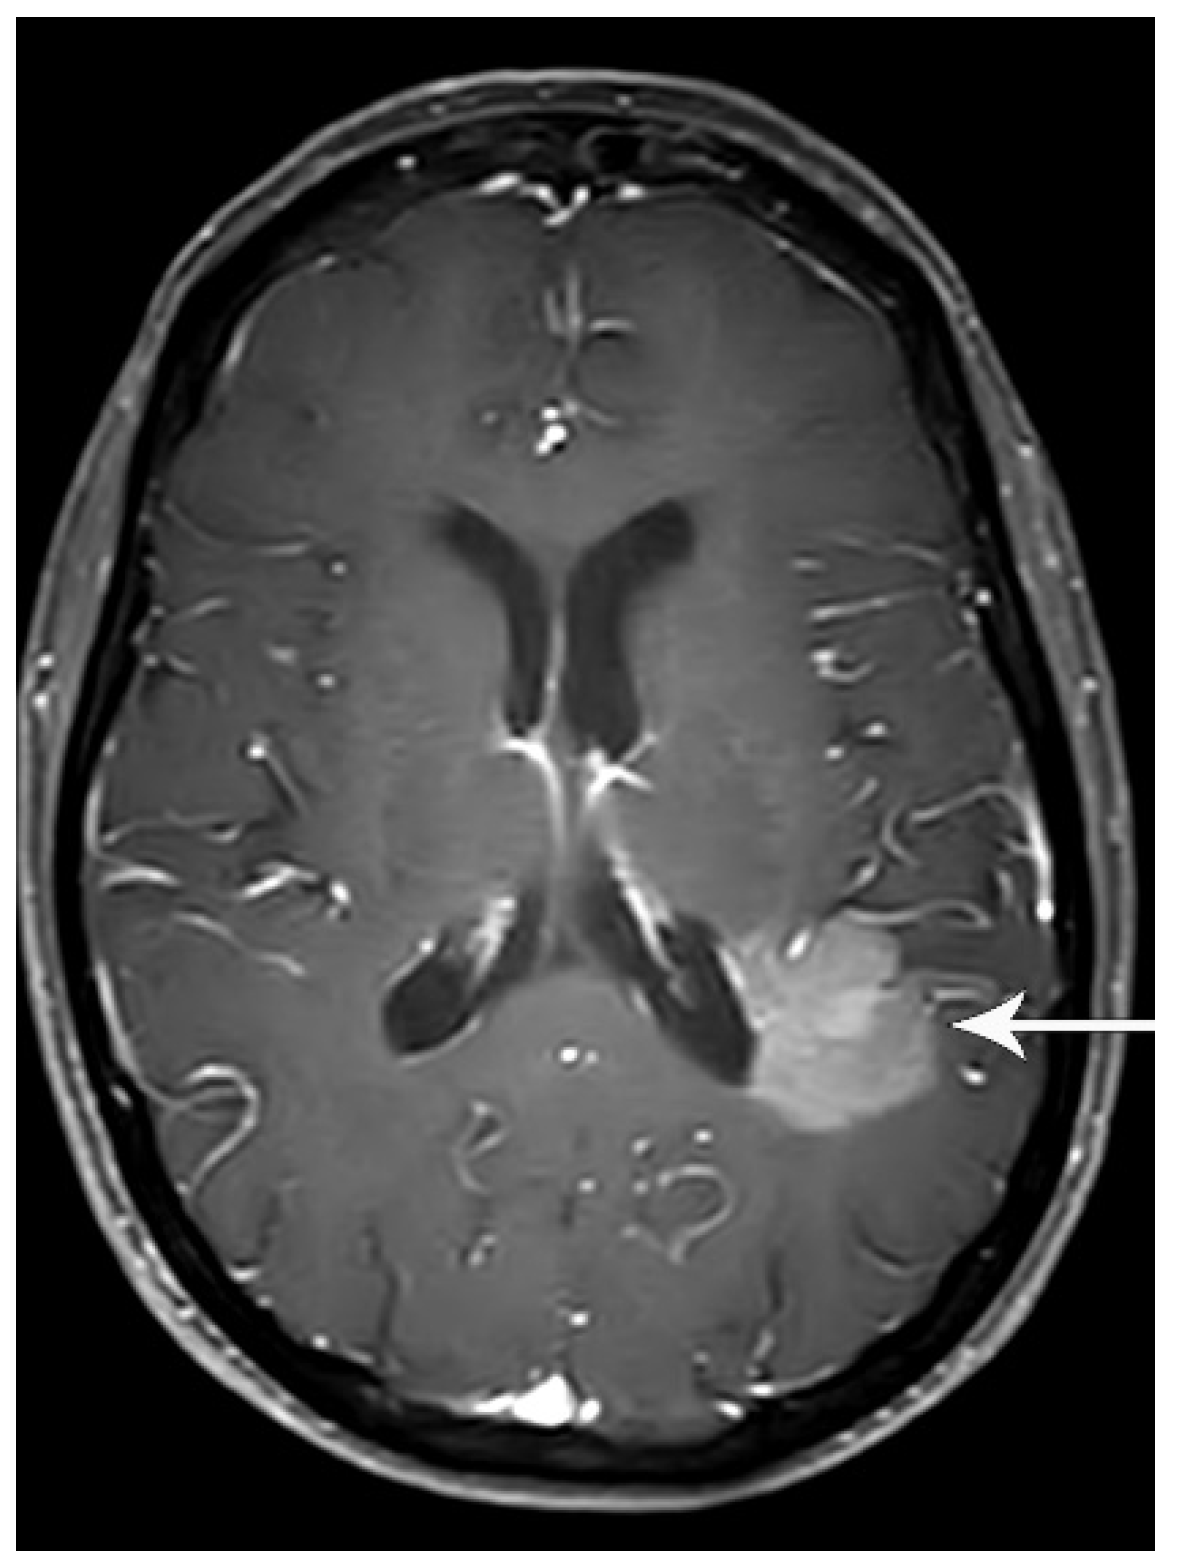

4. M Classification

- Diaz, M.E.; Debowski, M.; Hukins, C.; Fielding, D.; Fong, K.M.; Bettington, C.S. Non-small cell lung cancer brain metastasis screening in the era of positron emission tomography-CT staging: Current practice and outcomes. J. Med. Imaging Radiat. Oncol. 2018, 62, 383–388. [Google Scholar] [CrossRef]

- Hendriks, L.E.; Bootsma, G.P.; de Ruysscher, D.K.; Scheppers, N.A.; Hofman, P.A.; Brans, B.T.; Dingemans, A.M. Screening for brain metastases in patients with stage III non-small cell lung cancer: Is there additive value of magnetic resonance imaging above a contrast-enhanced computed tomography of the brain? Lung Cancer 2013, 80, 293–297. [Google Scholar] [CrossRef] [PubMed]

- Hochstenbag, M.M.; Twijnstra, A.; Hofman, P.; Wouters, E.F.; ten Velde, G.P. MR-imaging of the brain of neurologic asymptomatic patients with large cell or adenocarcinoma of the lung. Does it influence prognosis and treatment? Lung Cancer 2003, 42, 189–193. [Google Scholar] [CrossRef] [PubMed]